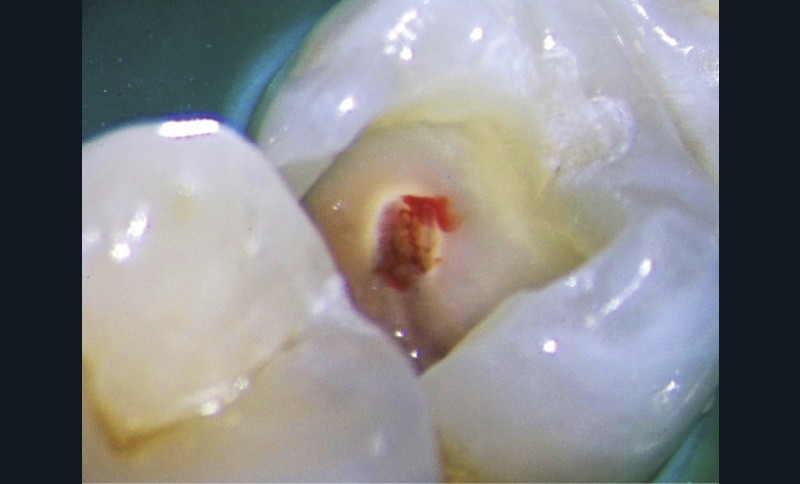

Le laser Er:YAG va permettre une élimination des débris en surface, une stérilisation, avec comme irrigation de l’eau stérile [36] et en coupant le spray, une hémostase avec la formation d’une couche de coagulation [37] propre à la formation d’un pont dentinaire au contact du biomatériau, qui peut être bio-actif, tel que la Biodentine (Septodont) (fig. 6a à d).

Protocole opératoire : sous anesthésie, une cavité suffisante à recevoir le biomatériau (2 à 3 mm) sous champ opératoire est réalisée. La désinfection au laser Er:YAG (40 mJ ; 20 Hz) sous spray, pendant 20 secondes, est alors mise en œuvre. S’en suit éventuellement une coagulation de 3 secondes, en coupant le spray, puis la mise en place du biomatériau Biodentine (Septodont). Il sera ensuite recouvert d’un matériau de restauration adéquate.